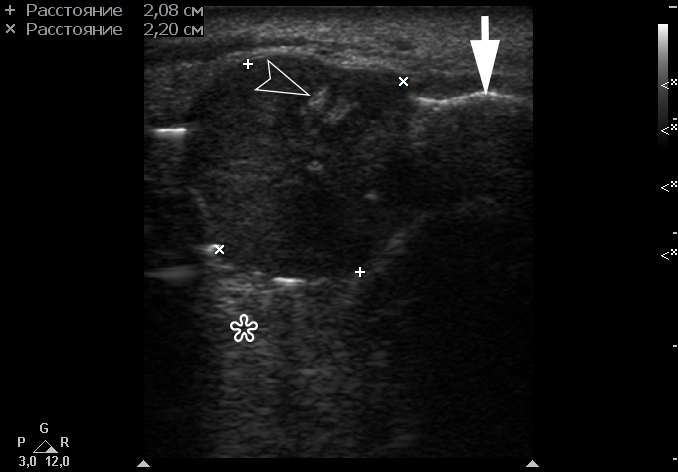

Gray-scale USG (Fig 4) revealed a unilocular, well-defined lesion with heterogeneous echogenicity. The lesion was measured 2.08 × 2.2 cm and located in a saddle-shaped position on the edentulous area of the anterior part of alveolar ridge of the mandible. The presence of multiple echoic areas and acoustic enhancement behind the neoplasm is noted.

FIGURE 4. Gray-scale ultrasound shows a unilocular, well-defined lesion with heterogeneous echogenicity. The lesion is measured 2.08 × 2.2 cm and indicated by “+” and “×” calipers. The lesion is located in a saddle-shaped position on the edentulous area of the anterior part of alveolar ridge of the mandible. Echoic area of bone formation is indicated by arrowhead. The area of the mandible on which the mass is located is indicated by an arrow and has a hyperechoic appearance. Acoustic enhancement is marked with an asterisk.

Color Doppler USG (Fig 5) showed prominent intralesional vascularity. Figure 6 demonstrates gray-scale USG of the lesion from two different angles, which allows for better visualization of echogenic areas (i.e., areas of ossification) within the lesion. It was not possible to adequately determine the area of the “stem” of the lesion.

FIGURE 6. Gray-scale sonograms of the lesion from two different angles (A, B). Sonograms show a hypoechoic lesion with multiple echoic areas (i.e., areas of bone formation). It is easy to distinguish areas of ossification (arrowheads) in the thickness of the lesion due to their echoic look. These two images demonstrate that gray-scale ultrasound is highly sensitive for detecting areas of ossification within a neoplasm such as PGCG.